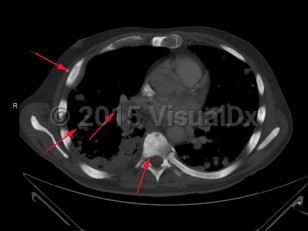

Metastatic prostate carcinoma

Prostate gland carcinoma that has disseminated. Metastatic prostate carcinoma is seen less frequently due to prostate-specific antigen screening, which enables early diagnosis of prostate cancer while it is still localized. Malignant cells can appear throughout the body as cancer advances, with the bones and lymph nodes more commonly affected.

In patients with bone metastasis, the axial skeleton is often involved. Common findings include bone pain, pathologic fracture, and spinal cord compression may be observed. Patients with lymph node involvement will present with regional or cervical lymphadenopathy. Masses may also be observed, especially in the neck. The skin, liver, and penis are also reported areas of involvement.